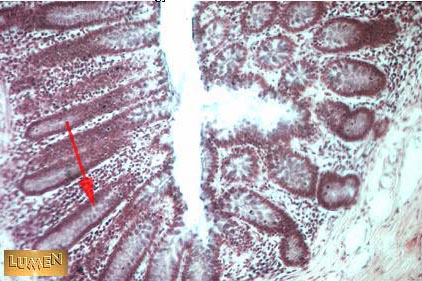

What is the structure indicated by the arrow?

Crypt of Lieberkuhn